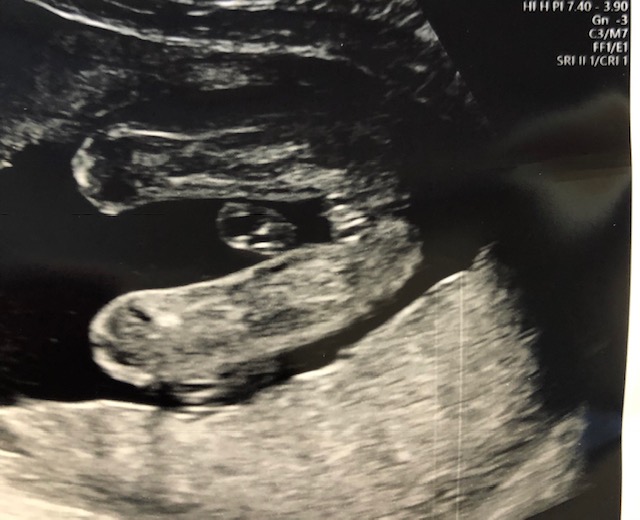

Here's our latest scan. None of my boys have looked like this, but thoughts on gender?

Girl. A few inches out is a piece of cord but that's a pretty clear shot of labia. The "three white lines" sign. :) Congrats!

Yes, I see that little something sticking out too, but it's totally unfamiliar, haha! Thank you, ladies. I won't officially OFFICIALLY know until the baby comes out, but I hope these signs stay true. I'm in shock. <3

We can be wrong though. REmember we only see what the tech captures on the screen and they can zoom in on some parts and obscure others, especially if they think you didn't want to know gender.

Still, I'll be pretty shocked if that's a boy. :)